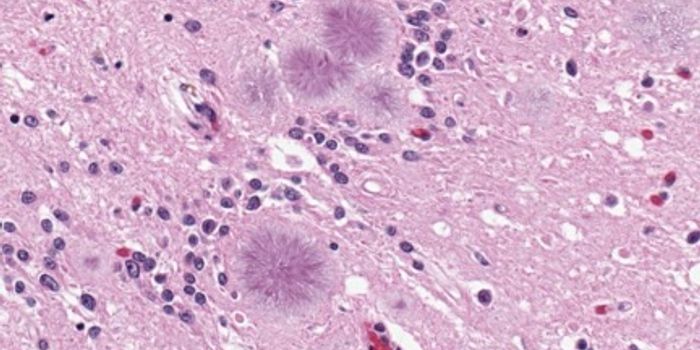

JUL 16, 2019Health & MedicineSarcoidosis is an inflammatory disease with the hallmark diagnostic feature being non-caseating granulomas--clumps ...

SEP 11, 2019Health & MedicineSarcoidosis is a multisystem inflammatory disease characterized by the formation of non-caseating granulomas in the ...